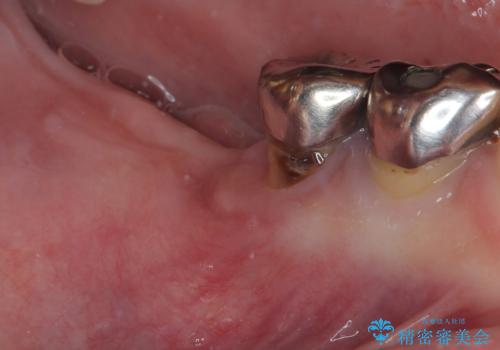

CTにより残存骨量を確認しインプラント埋入を行っていくこととしました。

今後手前の根管治療を行っている歯が歯根破折を起こして抜歯になる可能性を想定して手前の歯に平行にインプラント埋入を行っています。